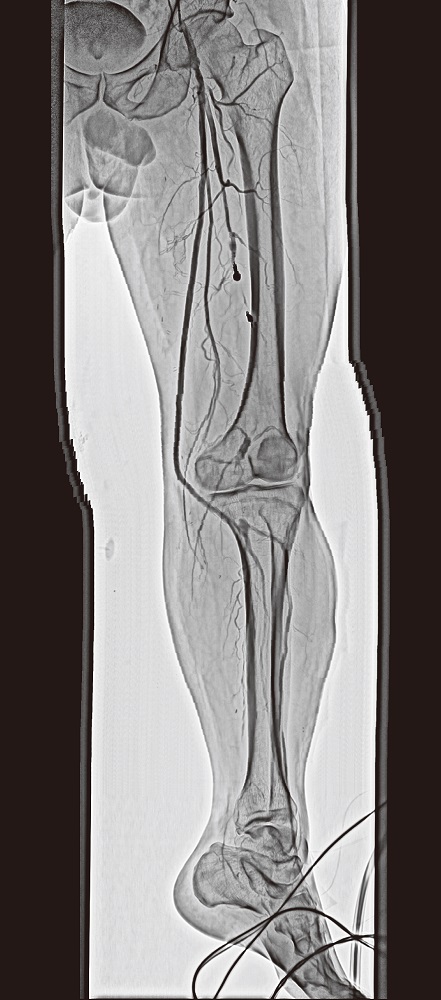

SCORE Chase (Option)

SCORE Chase ist eine Funktion für die Echtzeit-Betrachtung von peripheren Regionen. Die gesamte periphere Long-View-Aufnahme wird automatisch und ohne Zeitverzögerung zusammengefügt und angezeigt. Diese Anwendung ist für den SCORE-RSM- oder Digital-Acquisition-Modus verfügbar.